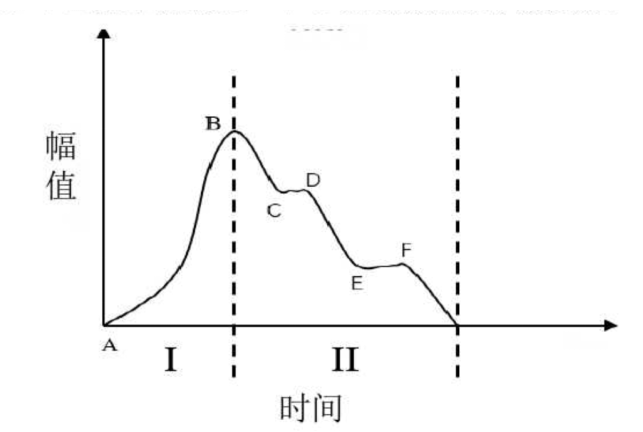

在营养物质的传输方面:营养物质从血液进入组织,仅靠血液的流动是不行的。实际上,脉搏波在心脏的跳动下大概有这样的波形:

脉搏波周期压力变化示意图,纵轴为压力幅值。AB对应上升支,之后对应减载支 | 图自[4]

每一次心脏跳动带来的脉搏波波面所到之处,都将有压力的一个上升支,随后迎来一个下降支。一升一降之间,完成了血液的流动和营养物质的传输。